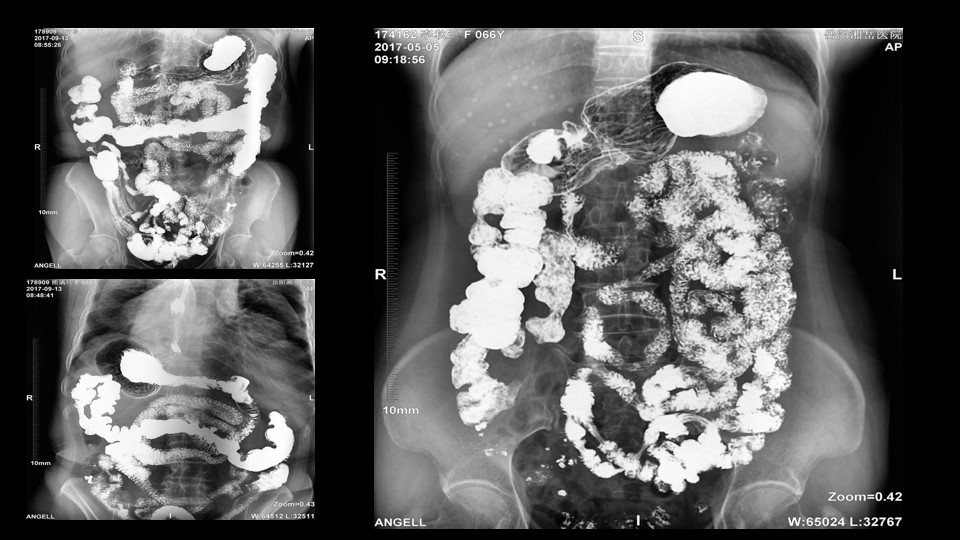

会议开始,岳阳市医学会放射分会副主委、湘岳医院放射科蔡雨主任,结合自身在放射影像的20多年经验,为参会嘉宾分享了动态DR在消化道造影中的应用价值。作为动态DR用户,蔡雨主任结合动态DR的实际拍片与操控经验,分享了动态DR技术在相关群体疾病检查上的独到优势和人文关怀。蔡雨主任说到:“随着内镜技术的发展以及CT、MR的发展,消化道造影在减少,但是这并不意味着消化道造影的价值在下降。以老年人为例,很多老年群体都患有严重的心肺疾病、或者消化道畸形,很多老年人本身就有糖尿病、高血压等等综合疾病,传统内镜的检查对于这类群体来说是一件难以忍受的痛苦,而动态DR的多项创新技术让这类群体的消化系统疾病筛查变得更为人性和精准。任何一个好的消化道造影,一定是患者、诊断医生、临床医生三方满意的结果。必一运动科技动态DR技术利用900万像素高清拍片、大幅面透视、高清点片、视频保存与回放等核心功能,完全满足临床对消化道气钡双重造影检查的需要。图像质量全面超越以往模拟胃肠机、影增数字胃肠机”。蔡雨主任全面演示了动态DR在食道造影、上消化道造影、小肠双对比造影、结肠气钡双对比造影中的应用,通过动态DR可以清晰获得临床诊断和评估的图像依据。

▲蔡雨主任使用动态造影图像示例